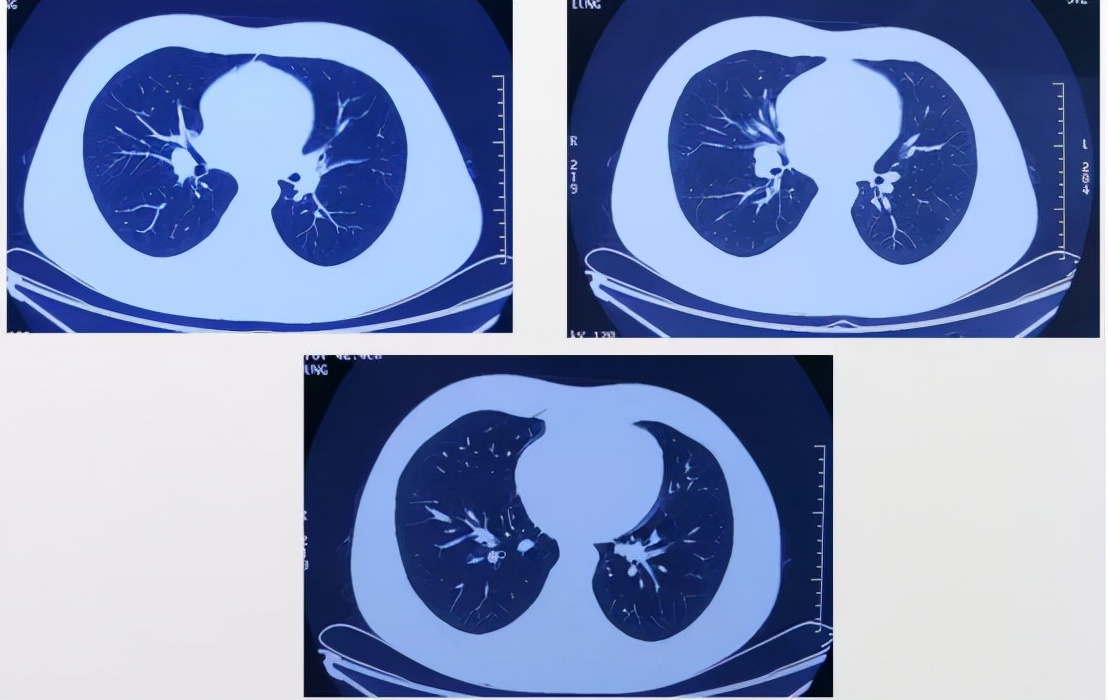

就诊于外地某三甲医院,行胸部CT(2020-09-30)检查提示右肺下叶前基底段少许小气道炎症,予「头孢克肟」治疗1个月,症状无明显好转,未进一步诊治。

入院前1月余(2021-6)患者出现活动后胸痛再发,部位为前胸,呈烧灼样疼痛,NRS 7分,向右侧上肢及左侧下肢放射,无压痛,以活动后和情绪激动后为著,持续3min后自行缓解。外院行运动平板试验阴性、超声心动图正常,胸部增强CT(2021-06-30)示右肺下叶前基底段实变影伴多发结节,轻度强化,纵隔及双侧腋下未见肿大淋巴结。后胸痛逐渐加重,多于变换体位后出现,持续5min后可自行缓解,伴胸闷、咳嗽,咳少量白痰,无咯血、盗汗,无乏力、消瘦。于外地某三甲医院住院,行PPD试验强阳性,血沉、肿瘤标志物、心脏CT、腹部超声、动态心电图未见异常。气管镜检查示左右主支气管及其各叶段支气管开口通畅,粘膜充血、水肿,可见少许脓性分泌物附着,诊断支气管粘膜慢性炎症,BALF抗酸染色、细菌、真菌培养阴性, mNGS NTM-DNA 35.59拷贝,MTB阴性,病理未见癌细胞;复查胸部CT示右肺中叶片状磨玻璃影,右肺门增大,右肺门向外支气管血管束增粗,右下肺基底段可见结节影,7区肿大淋巴结。外院住院期间体温波动于36.6-37.4℃,予左氧氟沙星静点、乙酰半胱氨酸雾化吸入治疗,症状无明显好转。患者自发病来,精神可,体力差,食欲可,睡眠差,二便正常,体重无明显变化。

外院CT(2020-09-30):

外院CT:

我们总结病例特点: 青年男性,慢性病程。既往体健进行性加重的胸痛,多与体位相关,活动加重,休息可缓解。呼吸道症状轻微,病程后期有低热,无其他系统性症状胸部CT提示右肺下叶轻度强化的阴影,及右肺门多发结节,沿支气管血管束分布,轻度强化,7区肿大淋巴结,无胸腔积液气管镜提示粘膜慢性炎症改变,BALF mNGS提示NTM可疑阳性。

陈起航主任 为我们深入解读了患者的胸部CT:

患者为年轻男性,病变为局灶性,位于右肺下叶基底段,为不规则的片状实变影,远端有小叶中心性分布的小结节,支气管近端可疑狭窄;纵膈窗提示右侧肺门淋巴结肿大。结合患者的年龄、呼吸道症状和肺内影像学特点,肺内病变应该首先应鉴别感染性病变,比如结核,当然并不是结核的好发部位,但结核的胸部影像学的表现很多,当然其他可疑的鉴别诊断很多,但是从发病率而言,我们不会首先考虑肿瘤。